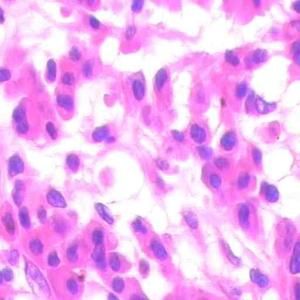

漿細胞型:占10%~20%。患者常伴有全身症狀,如發熱、乏力、體重減輕、貧血、紅細胞沉降率升高、血液丙種球蛋白增高和低白蛋白血症。淋巴結切除後症狀可消失。顯微鏡也可見見淋巴結內也顯示濾泡性增生但小血管穿入及濾泡周圍的淋巴細胞增生遠不及透明血管型明顯,一般無典型的洋蔥皮樣結構。本型的主要特徵為濾泡間各級漿細胞成片增生,可見Russell小體,同時仍有少量淋巴細胞及免疫母細胞。有人稱本型為透明血管型的活動期,可有TCRβ或IgH基因重排。有報導少數漿細胞型患者可並發卡波西肉瘤,以愛滋病伴發CD者多見。

(2)漿細胞型:占10%~20%。淋巴結內也顯示濾泡性增生但小血管穿入及濾泡周圍的淋巴細胞增生遠不及透明血管型明顯,一般無典型的洋蔥皮樣結構。本型的主要特徵為濾泡間各級漿細胞成片增生,可見Russell小體,同時仍有少量淋巴細胞及免疫母細胞。有人稱本型為透明血管型的活動期,可有TCRβ或IgH基因重排。少數患者病變累及多部位淋巴結,並伴結外多器官侵犯,病理上同時有上述兩型的特點稱為混合型。也有少數單一病灶者病理上兼有上述二型的特點,則為另一意義上的混合型。有報導少數漿細胞型患者可並發卡波西肉瘤,以愛滋病伴發CD者多見。